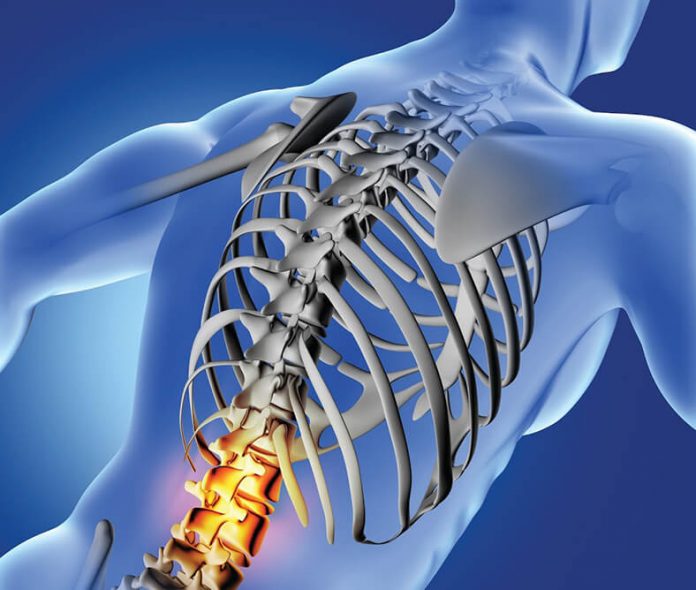

Οι παθήσεις της σπονδυλικής στήλης αποτελούν πεδίο έρευνας και θεραπευτικών εφαρμογών που εξελίσσεται ραγδαία.

Δεδομένου ότι τα προβλήματα τα οποία μπορεί να «γεννηθούν» από ή στην σπονδυλική στήλη είναι αρκετά, ένα πρωτοποριακό Θεραπευτήριο, όπως το Metropolitan Hospital, δεν αρκείται στη στελέχωσή του από κορυφαίους ιατρούς, αλλά διαθέτει και την πιο σύγχρονη τεχνολογία: το O-Arm. Ένα σύστημα αξονικής τομογραφίας που, σε συνδυασμό με τη χειρουργική πλοήγηση, εξασφαλίζει 100% ακρίβεια στη διαχείριση των πιο ευαίσθητων βλαβών, σε ανατομικώς εξαιρετικά επικίνδυνες περιοχές.

Παραμορφώσεις της σπονδυλικής στήλης

Οι συχνότερες παραμορφώσεις της σπονδυλικής στήλης, είναι η σκολίωση και η κύφωση. Όταν αυτές ξεπερνούν τις 40-45°, η χειρουργική θεραπεία δίνει πολύ καλά αποτελέσματα, όπως μόνιμη και σχεδόν πλήρη διόρθωση της σκολίωσης.

Ο Καθηγητής Γεώργιος Σάπκας, Διευθυντής Ορθοπαιδικός στο Metropolitan Hospital εξηγεί: «Σημαντική τεχνολογική εξέλιξη στη διεγχειρητική απεικόνιση είναι το O-Arm, το οποίο προσφέρει υψηλή ακρίβεια στην απεικόνιση και πλοήγηση, για την τοποθέτηση των υλικών σπονδυλοδεσίας, καθιστώντας την ασφαλή, σε μεγάλες παραμορφώσεις και σε ασθενείς με νεανική κύφωση».

Στους ενηλίκους, η παραμόρφωση επηρεάζει τη στάση του σώματος και συνοδεύεται από πόνο. Συχνά, υπάρχουν και συμπτώματα από τα κάτω άκρα, όπως ισχιαλγία, μουδιάσματα και δυσκολία στη βάδιση. Παράλληλα, οι ασθενείς πάσχουν και από άλλα νοσήματα όπως υπέρταση, στεφανιαία νόσο, διαβήτη, πνευμονοπάθειες, οστεοπόρωση κ.ά., τα οποία επιδεινώνονται με την παραμόρφωση και τον περιορισμό της δραστηριότητας. Η θεραπεία περιλαμβάνει τη διόρθωση της στάσης και την αντιμετώπιση των συμπτωμάτων, προκειμένου ο ασθενής να κινητοποιηθεί μία ημέρα μετά το χειρουργείο και να φροντίζει καλύτερα τα συνοδά προβλήματα υγείας.

Ελάχιστα επεμβατική χειρουργική εγκεφάλου και σπονδυλικής στήλης

Το τμήμα Ελάχιστα Επεμβατικής Χειρουργικής Εγκεφάλου και Σπονδυλικής Στήλης του Metropolitan Hospital στηρίζεται στη σύμπραξη άρτια εκπαιδευμένων νευροχειρουργών και ορθοπαιδικών, καθώς και στον υπερσύγχρονο εξοπλισμό. Με το O-Arm είναι εφικτές οι ελάχιστα επεμβατικές παρεμβάσεις σε παθολογίες της σπονδυλικής στήλης αλλά και του εγκεφάλου. Ογκολογικά, αντιμετωπίζονται οι πρωτοπαθείς και δευτεροπαθείς όγκοι. Tραυματολογικά, αντιμετωπίζονται τα κατάγματα, αλλά και απλά εκφυλιστικά προβλήματα, όπως δισκοπάθεια και στένωση σπονδυλικής στήλης. Το O-Arm «ξεδιπλώνει» στο χειρουργό τη δύσκολη και, πολλές φορές, «παράλογη» ανατομία της σπονδυλικής στήλης, χάρη στην προβολή της περιοχής σε τρία επίπεδα, σε πραγματικό χρόνο. Η χρήση του O-Arm εκμηδενίζει τις τεχνικές δυσκολίες και παρέχεται η δυνατότητα ασφαλούς επέμβασης για ασθενείς υψηλού κινδύνου, καθώς και μείωσης της νοσηρότητας.

Ο κ. Σπύρος Σκριβιλιωτάκης, Ορθοπαιδικός Χειρουργός, Διευθυντής Α’ Κλινικής Σπονδυλικής Στήλης και Υπεύθυνος Τμήματος Ενδοσκοπικής Χειρουργικής Σπονδυλικής Στήλης του Metropolitan Hospital συμπληρώνει: «Με το O-Arm, δύσκολες περιοχές (στενοί αυχένες, ανατομικές παραλλαγές, υψηλότερα επίπεδα αυχενικής και θωρακικής μοίρας) καθίστανται προσιτές με ακρίβεια και αξιοπιστία, εκμηδενίζοντας την πιθανότητα τραυματισμού νευρικών στοιχείων».

Μόνο πλεονεκτήματα για τον ασθενή

Χάρη στο συνδυασμό υπερσύγχρονου εξοπλισμού και ομάδας έμπειρων ιατρών, οι επεμβάσεις έχουν καταστεί αξιοσημείωτα ασφαλείς σε σχέση ακόμα και με το πρόσφατο παρελθόν. Καταστάσεις όπως επίσης, σπονδυλική στένωση, σπονδυλόλυση, σπονδυλολίσθηση, σκολίωση προσεγγίζονται ώστε να ευοδώσουν το καλύτερο αποτέλεσμα για τον ασθενή. Ο χρόνος νοσηλείας καθώς η πιθανότητα μετεγχειρητικών επιπλοκών έχουν μειωθεί στο ελάχιστο. Ο όγκος εργασιών της ομάδας του Metropolitan Hospital αυξάνεται συνεχώς με αποτελέσματα εφάμιλλα με αυτά εξειδικευμένων κέντρων του εξωτερικού.